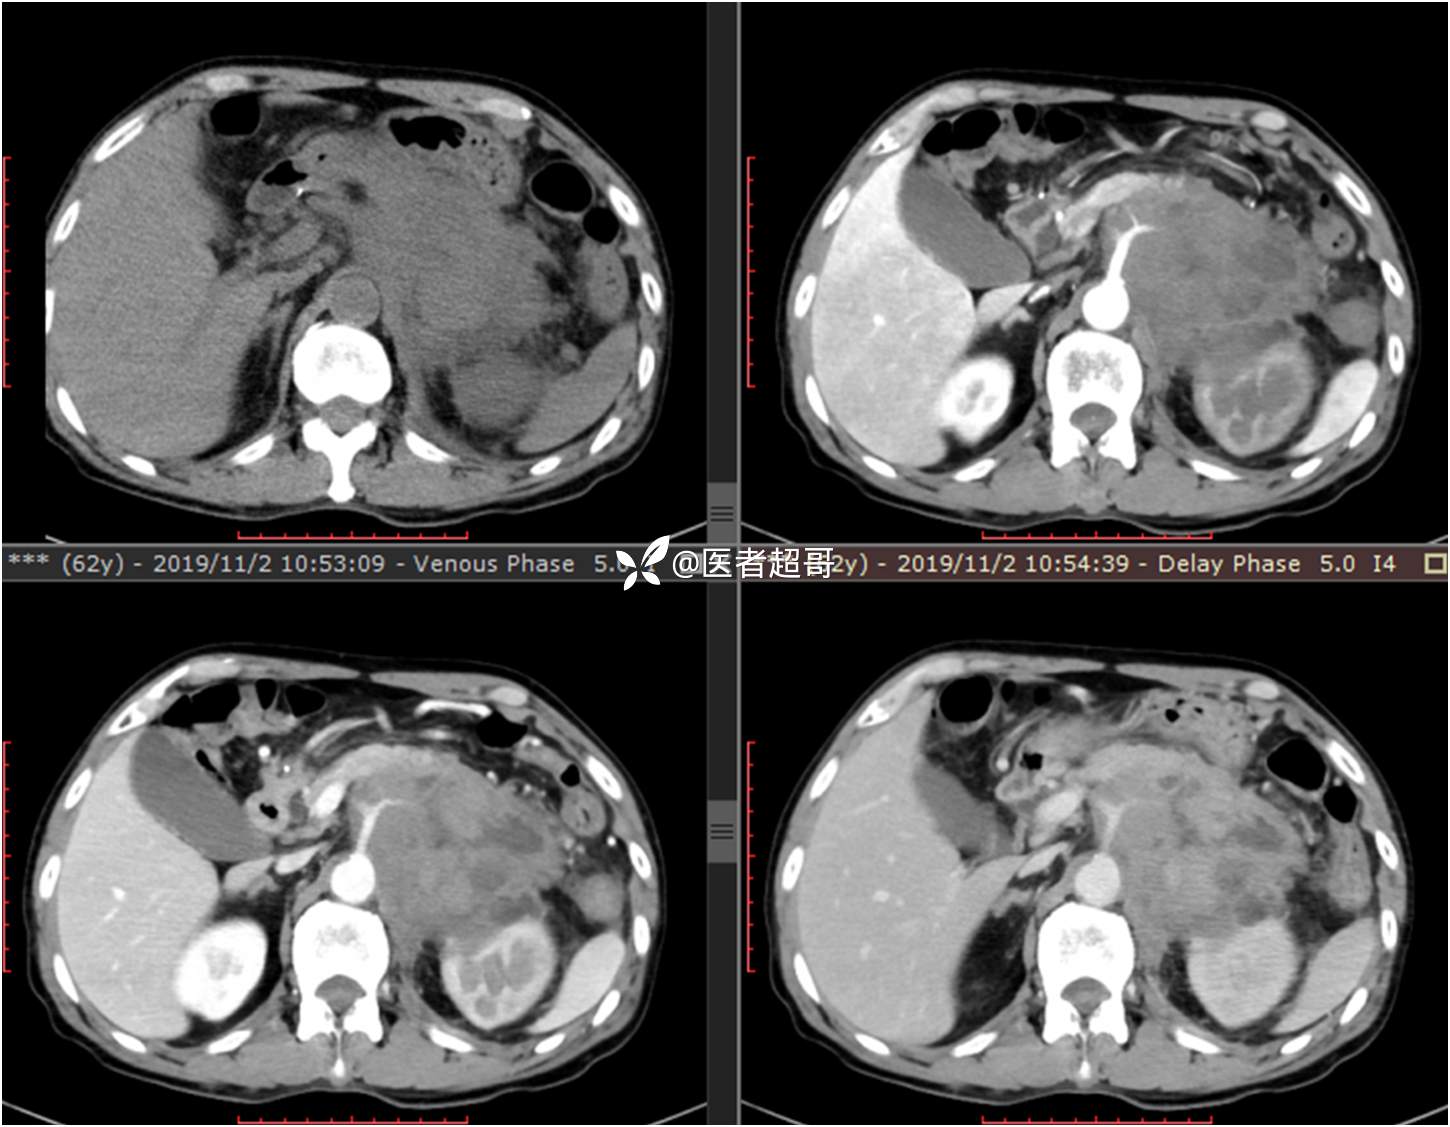

现病史:患者于1月前无明显原因及诱因出现左上腹部疼痛,为间断性疼痛,无恶心、呕吐,无寒战、高热,无腹胀、腹泻等伴随症状,在外未行特殊处理,患者于1周前自觉疼痛加重,为求诊治患者曾就诊于市东城医院,行全腹部强化CT提示:左肾上腺区肿块,符合恶性肿瘤侵犯左肾、胰腺及腹膜后大血管CT表现,行保守治疗,症状缓解,今患者为求进一步诊治,来我院就诊,行腹膜后占位穿刺活检病理提示:(腹膜后占位穿刺)小细胞背景内见细胞浆红染的神经节样细胞,建议到病理科加做免疫组化进一步明确诊断,遂以“腹膜后肿物”收入院,患者自发病以来,神志清,精神可,饮食、睡眠差,大小便正常,体重未见明显改变。